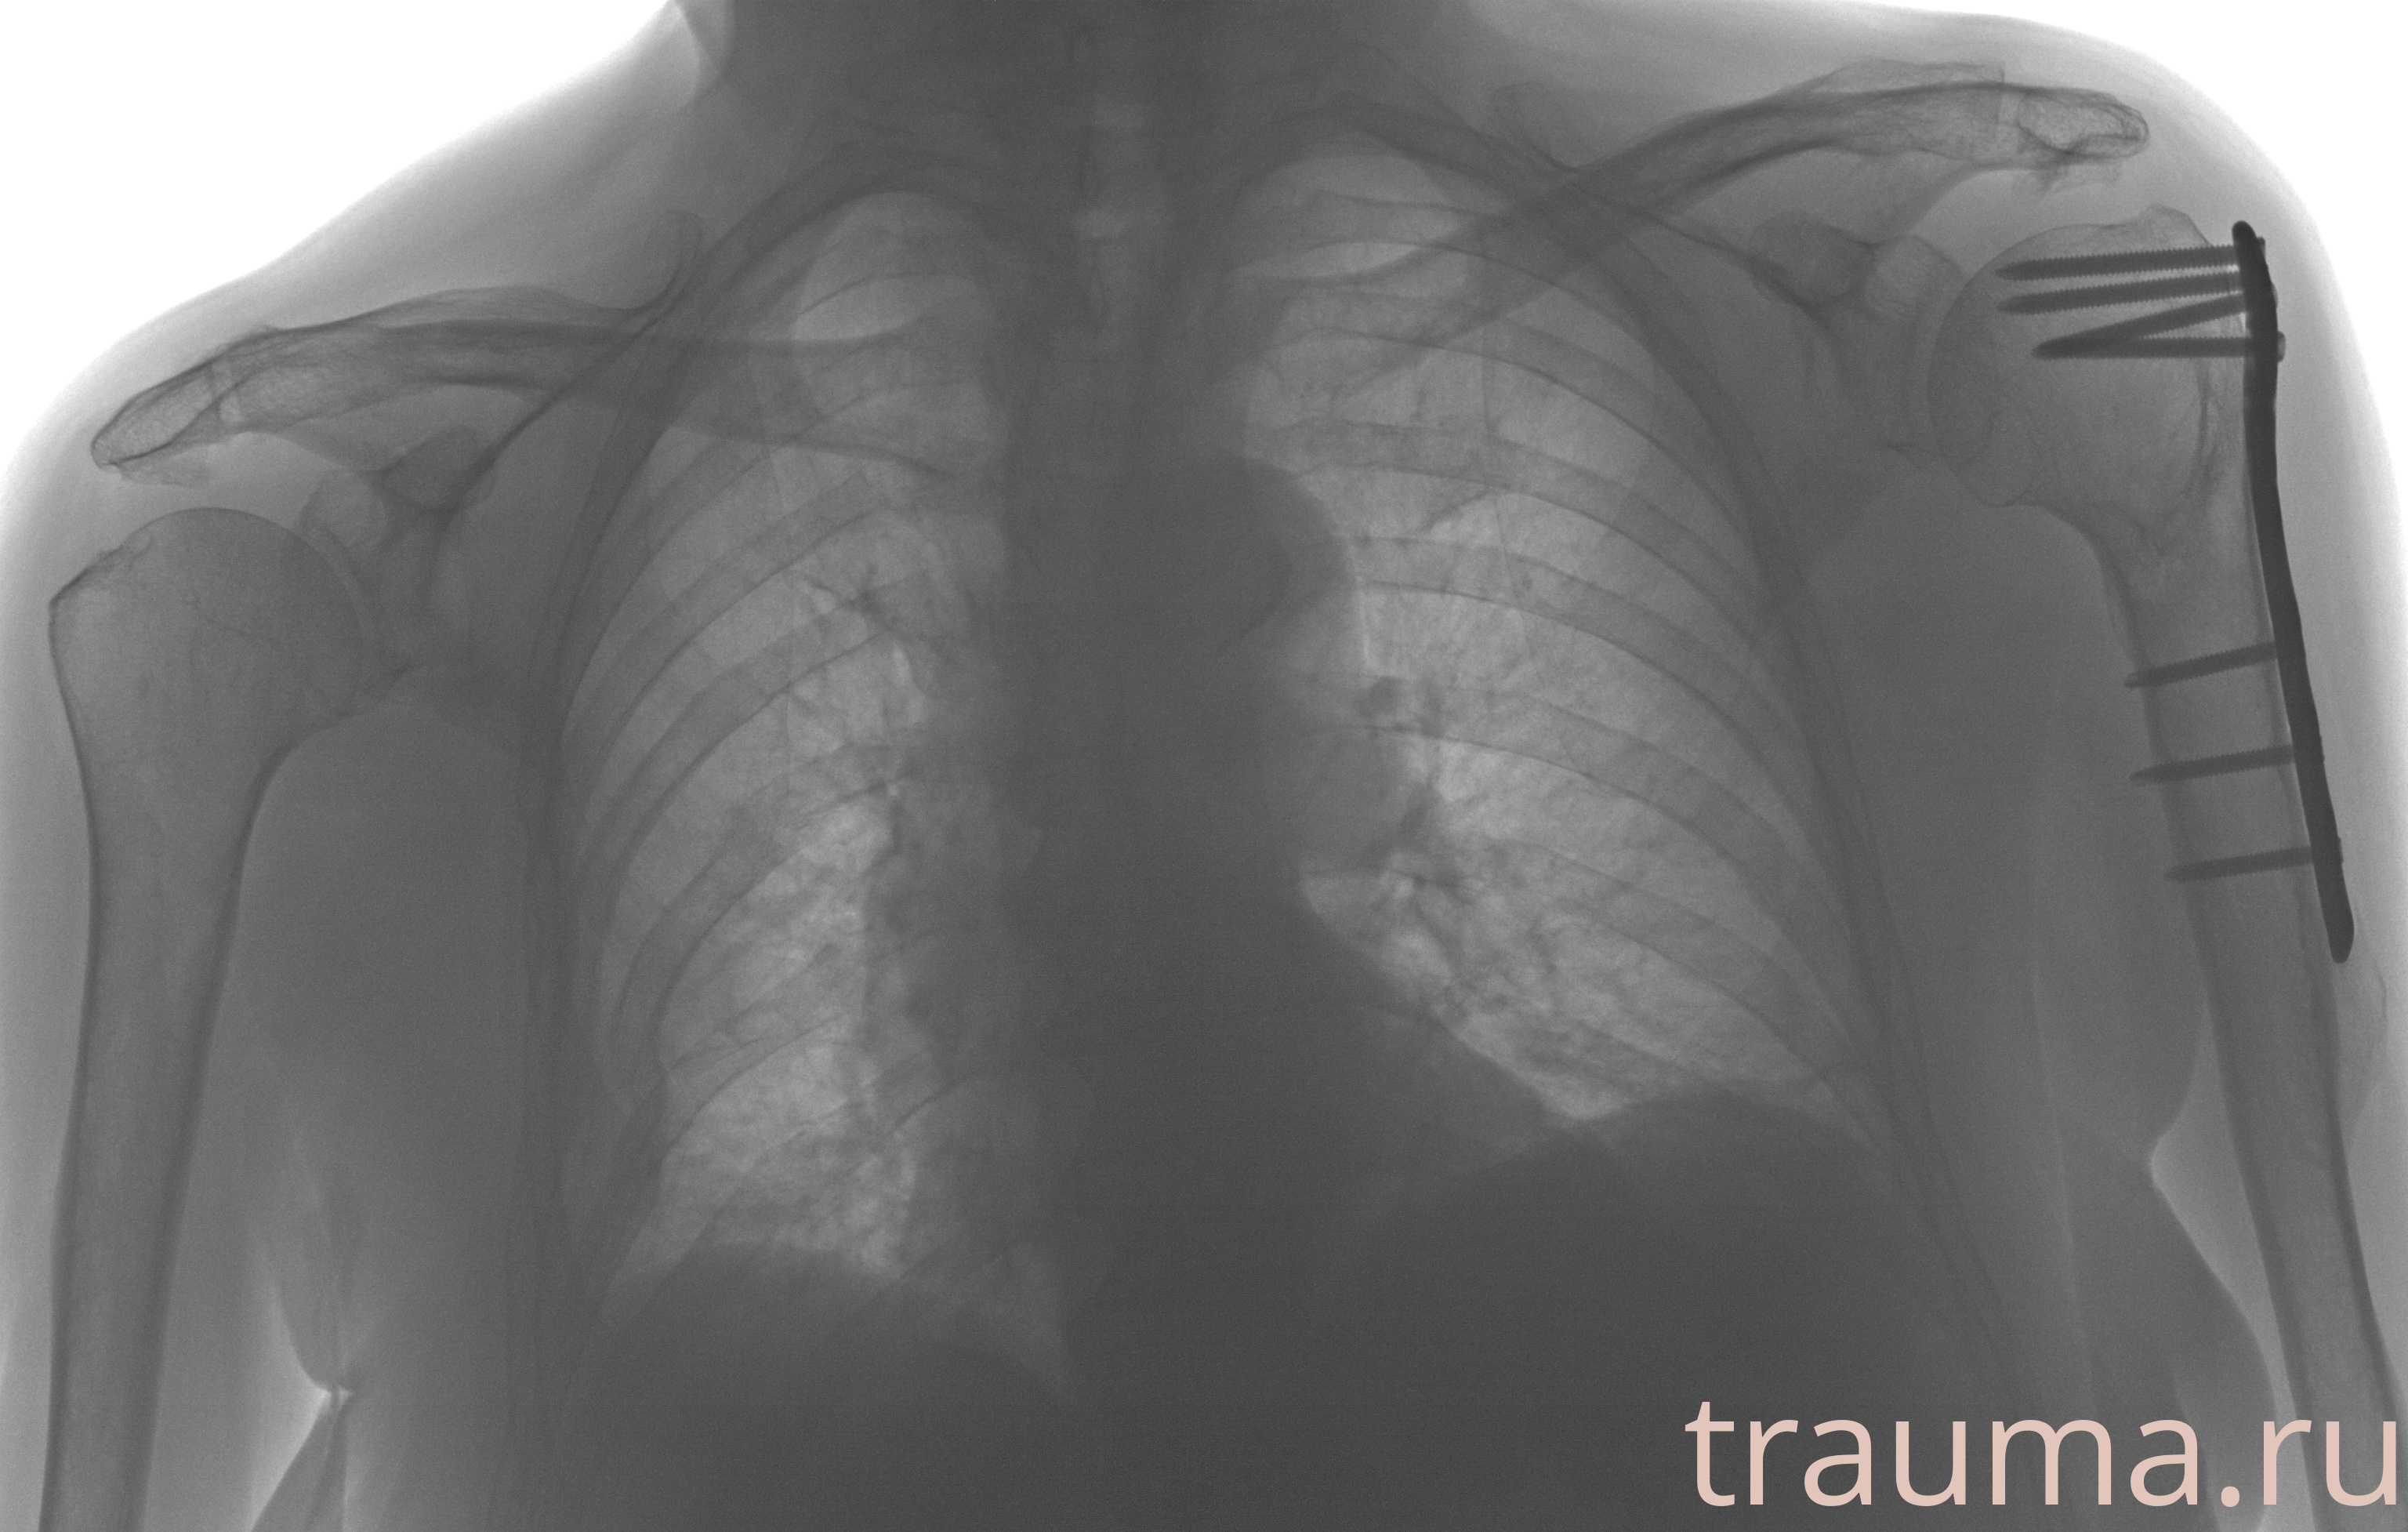

Рентгенограммы

Рентген на дому: по вашему адресу приезжает врач-рентгенолог, травматолог-ортопед с мобильным рентгеновским аппаратом, проводит диагностику травмы или заболевания, делает необходимые рентгенограммы, дает рекомендации по дальнейшему лечению. Получить качественные снимки в домашних условиях возможно благодаря уникальной методике, разработанной МосРентген Центром для института  Склифосовского

при переломе шейки бедра и пневмонии от компании МосРентген Центр - партнера Института имени Склифосовского